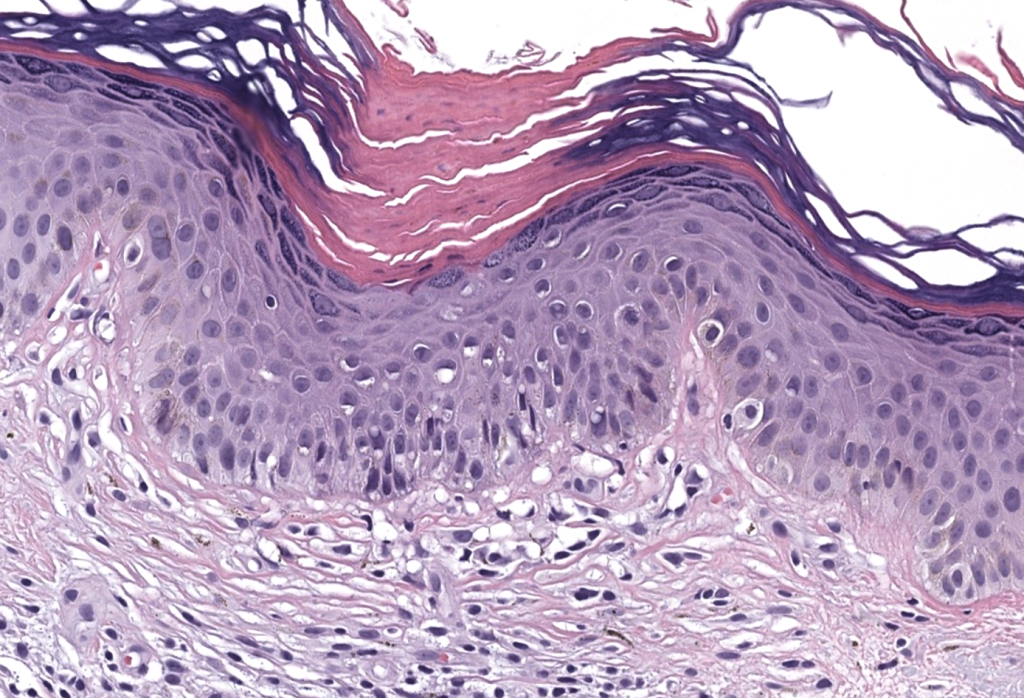

- Grupo heterogéneo de trastornos de queratinización caracterizados clínicamente por placas/pápulas anulares con borde hiperqueratósico y atrofia central, e histológicamente por la lamela cornoide (cornoid lamella). Vargas-Mora 2020, Kostopoulos-Kanitakis 2025

- Biopsia: punch/incisional del borde (ideal 4–6 mm incluyendo cresta). Vargas-Mora 2020